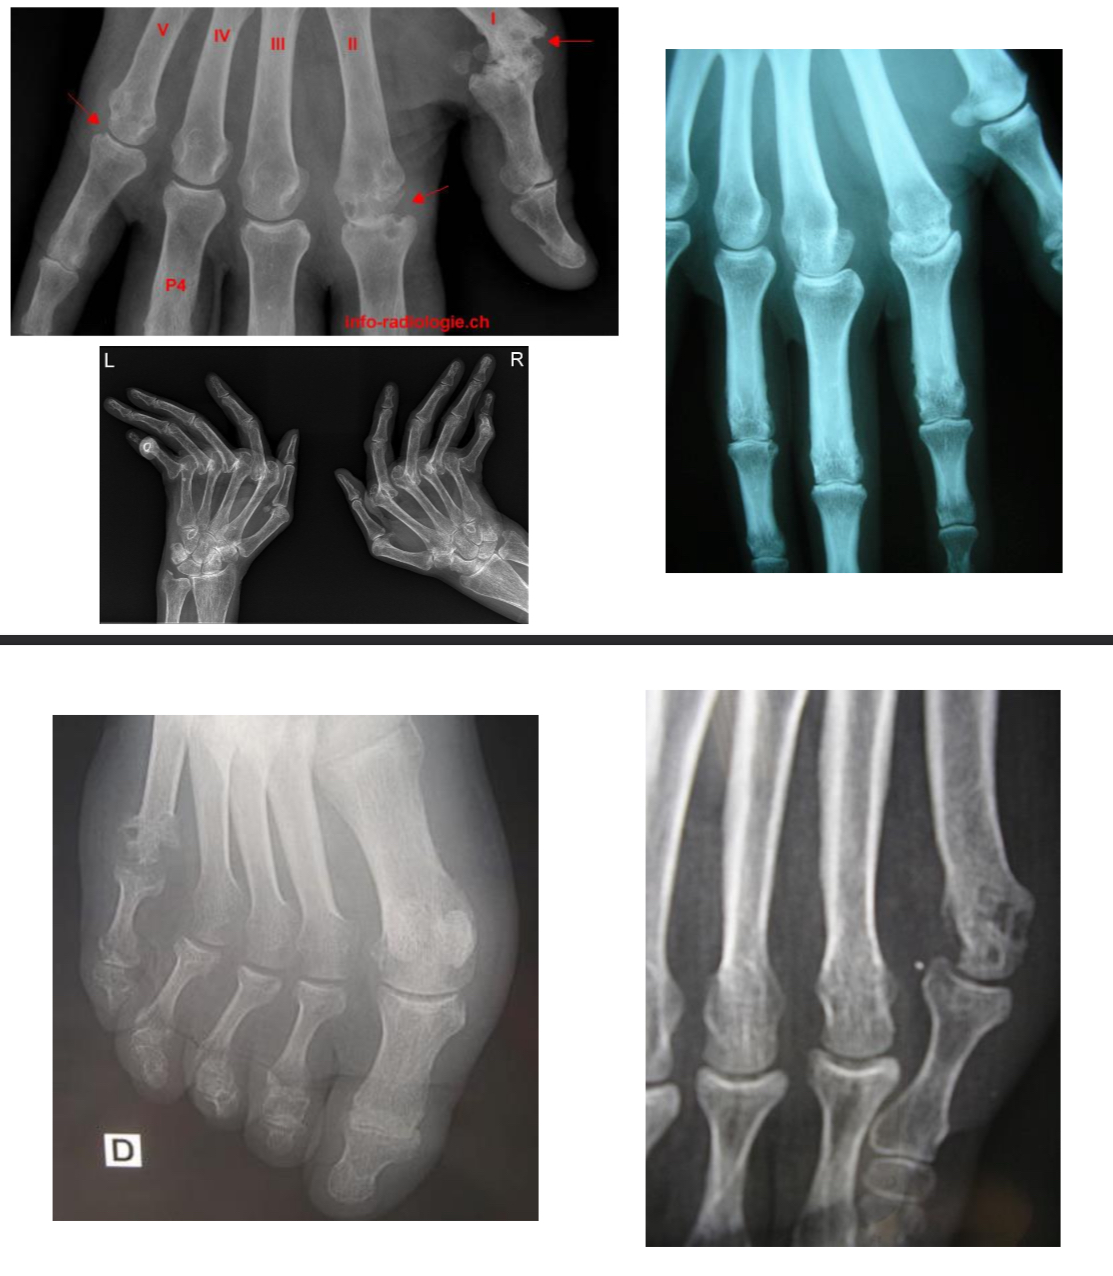

POLYARTHRITE RHUMATOÏDE

= réponse immunitaire incontrôlée : production d’auto-anticorps comprenant le facteur rhumatoïde (FR) et les auto-anticorps anti-protéines citrullinées (ACPA), réactions inflammatoire membrane synoviale (synovite)

Radio :

normale si PR débutante

Mains et poignets : F

Pieds : F+ 3/4

Autres articulations douloureuses : F + P

Thorax:bilan pré-T

Lésions structurales : érosions osseuses, pincement des interlignes articulaires (carpe, MCP, IPP et MTP)

Écho : recherche épanchement liquidien intra-articulaire, synovite, ténosynovite, érosions osseuses infra-radio

PR

destruction articulaire de la 5e MTP avec érosions multiples